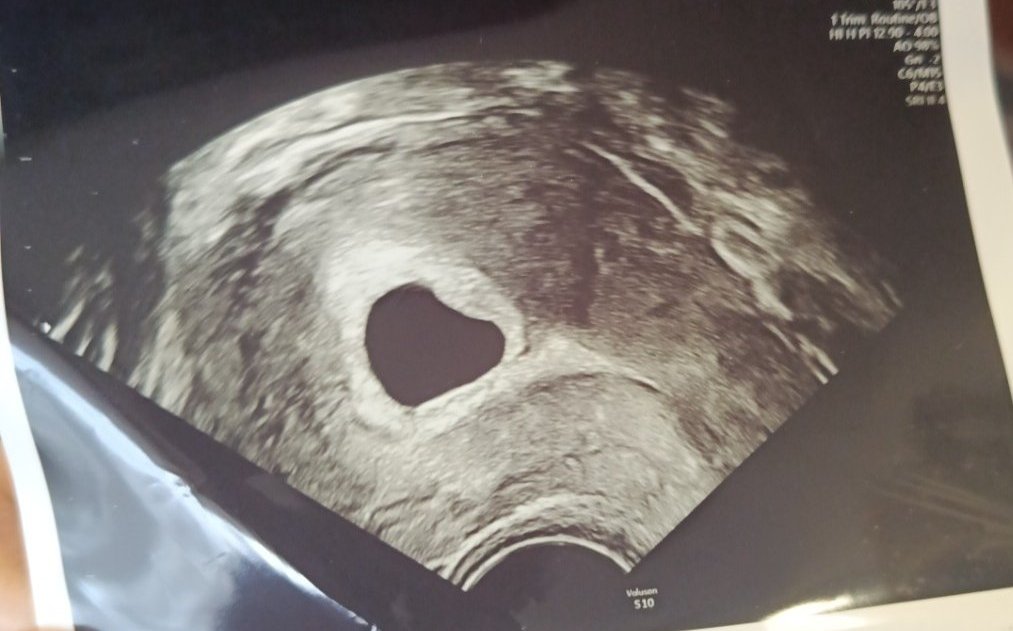

• Мнения: 203

Момичета здравейте тази снимка е от минала седмица от преглед в петък отново съм на преглед.Видя се само плоден сак в 6г.с.

Вие какво мислите ? Какво да очаквам ?

На снимката аз виждам плоден сак но вътре е празен не се вижда даже жълтъчно мехурче ,дано е рано да се види. Аз съм в същото положение снимката ми е подобна по МЦ бях в 7 гс о лекаря измери 6 гс. Това беше миналата седмица. В четвъртък пак ще ходя за да видим има ли вече нещо в сакчето… както и преди бях писала тук апаратурата му е доооста стара но пък невероятен специалист .Моята снимка и с доста лошо качество но като се загледам мисля че виждам нещо вътре